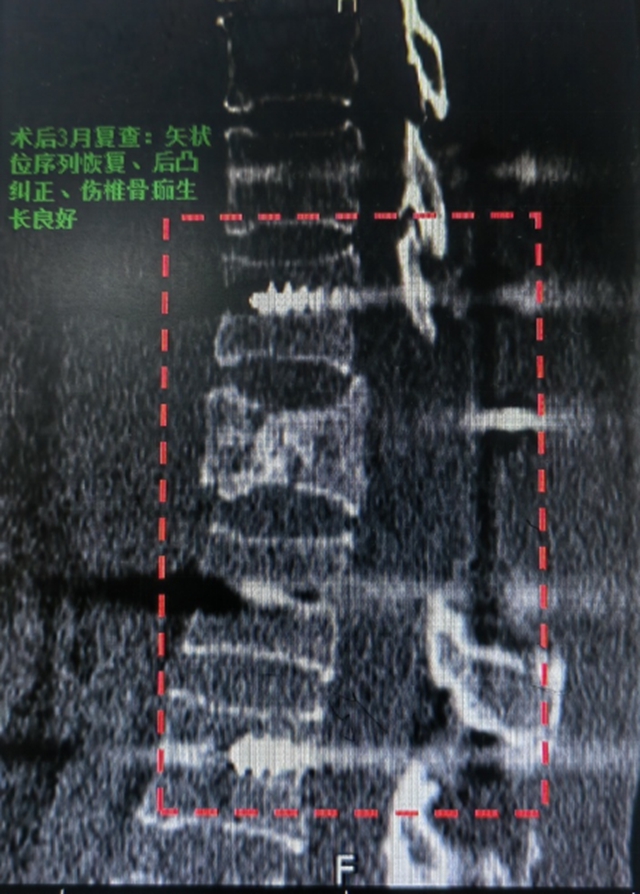

术后3个月,王女士返院复查时的情况令人振奋:

双下肢可自主抬离床面,肌力恢复至3级(可抗重力运动);

在辅助下可独立站立并短时支撑;

感觉功能部分恢复,康复信心大幅增强。